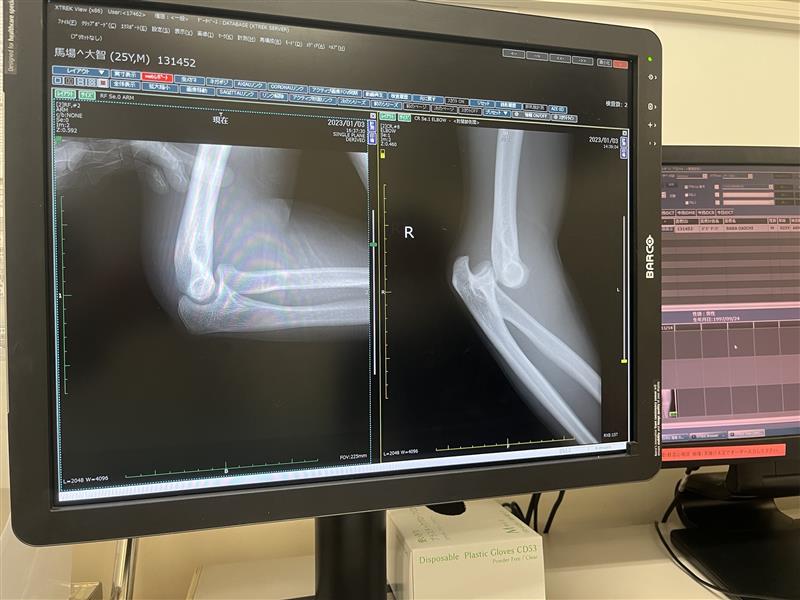

3年目は年明け早々に肘の脱臼。

この時はわりと激しく転倒し、後続車に遊ばれてしまいました。

以前もブログでも紹介しましたが唯一プロテクターの無い箇所の怪我でした。

プロテクターの重要性を我が身をもって体験できたのはいい経験だったと思います。